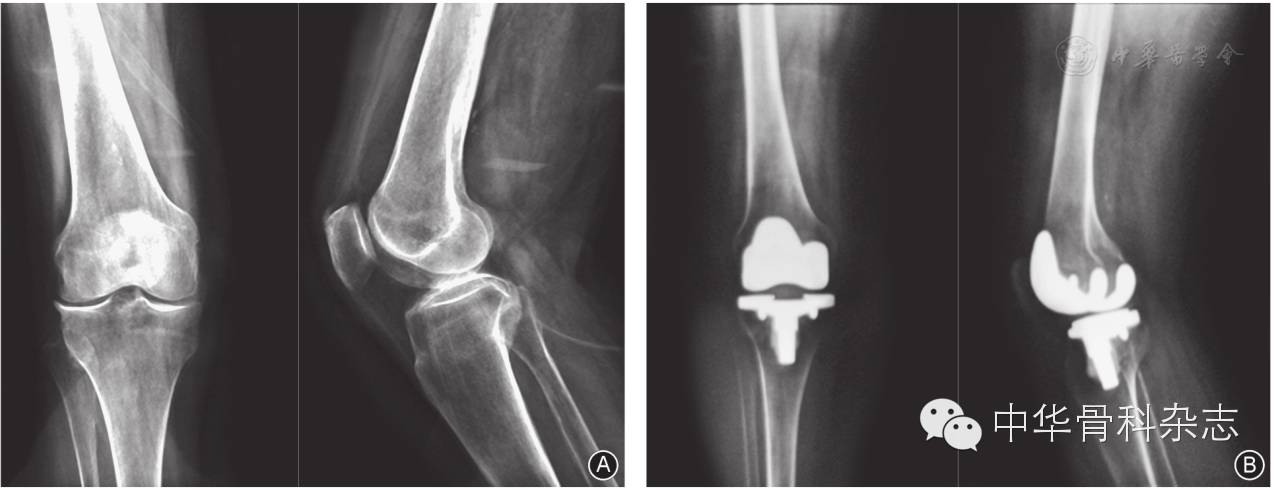

固定平台组与旋转平台组患者的膝关节活动度由术前72.8°±13.1°和71.2°±12.8°提高至末次随访时106.5°±9.8°和115.4°±7.9°,差异有统计学意义(P<0.05,表2)。X线股胫角由术前16.8°±5.3°和15.2°±4.7°降至末次随访时5.6°±2.3°和5.2°±2.1°;HSS膝关节评分由术前(47.5±7.1)分和(49.6±8.9)分提高至末次随访时(89.1±4.6)分和(90.2±5.3)分;SF-36评分由术前(52.3±15.4)分和(50.1±17.9)分提高至末次随访时(81.6±12.3)分和(82.2±14.5)分,差异均有统计学意义(P<0.05,表2图1图2)。

图2 女,67岁,右侧膝关节骨关节炎伴外翻畸形 A 术前右膝正、侧位X线片示外侧关节间隙狭窄,边缘骨赘增生,胫股角20° B 应用旋转平台假体全膝关节置换术,术后正、侧位X线片示膝外翻畸形矫正,下肢力线恢复正常,假体稳固在位